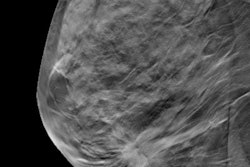

Adding digital breast tomosynthesis (DBT) to digital mammography (DM) improves the sensitivity and specificity of breast cancer screening -- and these improvements are also present when synthesized 2D images are used, according to a study published online February 19 in Radiology.

The study data come from the Oslo Tomosynthesis Screening Trial (OTST) and demonstrate that synthesized 2D images can be trusted for screening, wrote a team led by Dr. Per Skaane, PhD, of the University of Oslo in Norway. The sensitivity and specificity results of the trial across a variety of breast cancer screening combinations have not been previously reported.

"The use of synthetic mammography rather than digital mammography in combination with digital breast tomosynthesis resulted in little change in either sensitivity or specificity, which indicates that synthetic mammography might be a viable alternative to digital mammography when using digital breast tomosynthesis, although additional studies are needed," the group wrote.

Establishing that 2D mammography is comparable to digital mammography is important because combining DM with DBT doubles the radiation dose women receive in a mammogram, Skaane and colleagues noted.

"If synthetic mammography could be used rather than digital mammography with DBT, a screening examination could be performed at a radiation dose similar to that of digital mammography," they wrote. "There have been positive reports on the use of synthetic mammography in screening, but, to our knowledge, this study is the first large prospective trial comparing synthetic mammography and digital mammography in combination with DBT for the same set of cases."